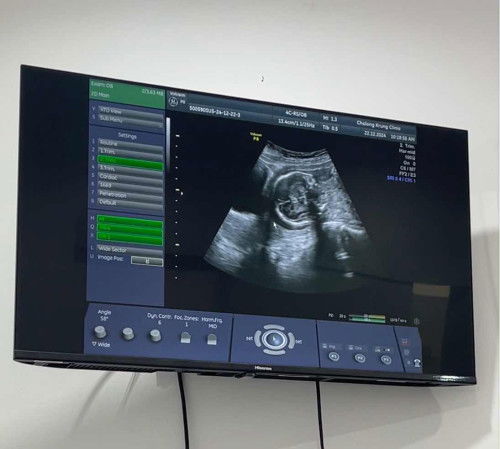

21W น้องเอาหัวลงต่ำ เสี่ยงคลอดก่อนกำหนด ต้องเหน็บยากันแท้ง

21W น้องเอาหัวลงต่ำ เสี่ยงคลอดก่อนกำหนด จากในภาพคือหัวน้องเบียดอยู่กับกระเพาะปัสสาวะ แถวๆลูกศรชี้คือปากมดลูก หมอจ่ายยากันแท้งมาให้เหน็บ 14วัน แล้วนัดไปดูอีกทีว่าเหน็บยาแล้วเป็นยังไง ถ้ายังเสี่ยงสูงอยู่หมอจะพิจารณาให้หยุดงานแล้วนอนพักอยู่บ้านค่ะ แม่ท่านไหนเคยเจอแบบนี้บ้าง น้องมีโอกาสจะเอาหัวขึ้นอีกมั้ยคะ หรือทำได้แค่ประคับประคองน้องไว้ให้ได้นานที่สุด ตอนนี้กังวลมากๆค่ะ 🥺